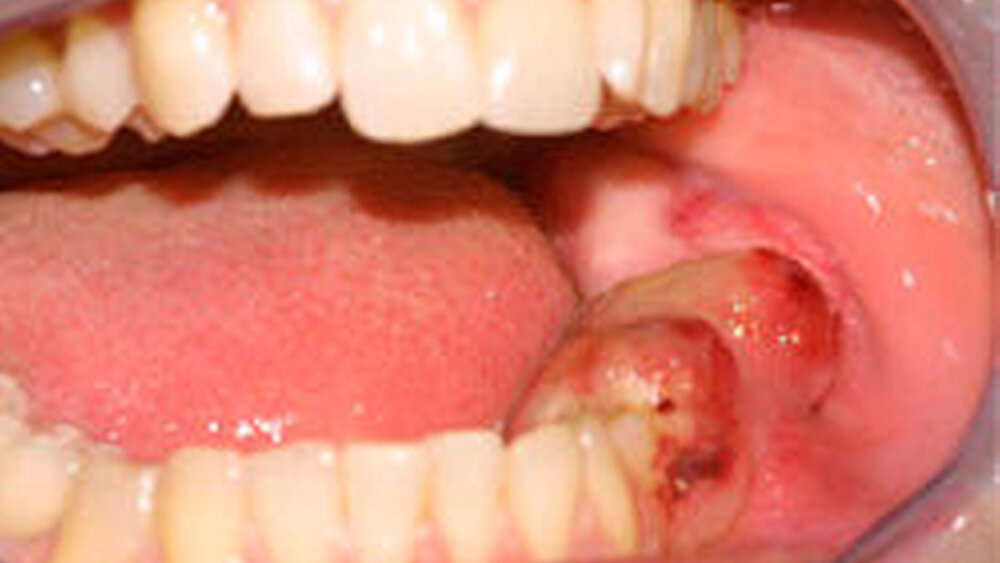

Eine 32-jährige Patientin stellte sich mit einer Blutung aus einer marginalen Gewebevermehrung am Gaumen vor. Es bestand eine Schwangerschaft im neunten Monat. Bei der klinischen Untersuchung zeigte sich eine zirka 0,7 cm große, weiche, stark vaskularisierte Raumforderung, die adhärent zum Parodont in Regio 16 war (Abbildung 1). Der Tumor war weich, livide und unter Spateldruck partiell exprimierbar. Innerhalb weniger Tage änderte sich der Aspekt der Oberfläche. Die Läsion blasste merklich ab (Abbildung 2) und die Gefäße erschienen weniger prominent. Obwohl die Morphologie sehr typisch für eine Schwangerschaftsepulis war, fiel die Entscheidung zur Entfernung der Läsion vor dem Hintergrund der Blutungsanamnese und der Tatsache, dass zwei Wochen vor dem errechneten Geburtstermin bei zeitgerechter Kindesentwicklung keine wesentlichen Gefahren durch die Exzision zu erwarten waren. Das Gewebe wurde in Lokalanästhesie entfernt (Abbildung 3). Prä- und postoperativ wurde ein Cardiotokogramm zur Kontrolle der Schwangerschaft geschrieben.

Die Schwangerschaftsepulis ist eine Sonderform solcher reaktiv-hyperplastischen Gingivaläsionen, wobei auch hier, trotz deutlicher Häufung in der Schwangerschaft mit einer Prävalenz von 0,2 bis 9,6 Prozent aller Schwangeren [Bhashkar, Jackoway et al., 1996], keine kausalen Zusammenhänge aufgeklärt sind. Der Zeitpunkt des ersten Auftretens liegt meist im zweiten oder dritten Schwangerschaftsmonat [Tumini, Di Placido et al., 1998]. Histologisch unterscheiden sich Schwangerschaftsepulitiden nicht von Epuliden außerhalb der Schwangerschaft. Anders als bei der primär harmloseren Gingivitis kann es hier in der Folge der Erkrankung allerdings zu Ulzerationen und vor allem zu ossären Destruktionen am Parodontalapparat kommen. Neben den schwangerschaftsassoziierten Phänomenen am marginalen Parodont werden selten auch extrem schnell und destruktiv wachsende Riesenzellgranulome im Zusammenhang mit Schwangerschaften beobachtet [O’Regan, Gibb, 2001]. Abbildung 5 zeigt die ossäre Destruktion im Kieferwinkel durch ein Riesenzellgranulom unter Gravidität, wobei die Patientin sechs Jahre später im Laufe einer erneuten Schwangerschaft eine zweite Läsion entwickelte.

Es soll an dieser Stelle aber auch darauf hingewiesen werden, dass mit der Erwartung typischer schwangerschaftsbezogener Veränderungen auch folgenreiche diagnostische Verwechslungen einhergehen können. Abbildung 6 zeigt ein Beispiel eines Sarkoms bei einer 33-jährigen Schwangeren, das zunächst als Schwangerschaftsepulis fehlgedeutet wurde.